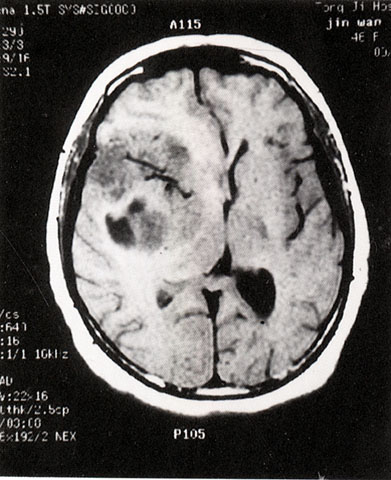

FH1051 脑胶质瘤(MRI)

光盘检索编码 FH1051  函授作业图编号 1051

图  名 脑胶质瘤(MRI)

导  学 与图1051、1052、1053、1054、1055为同一患者

讨 论 题 阅图分析